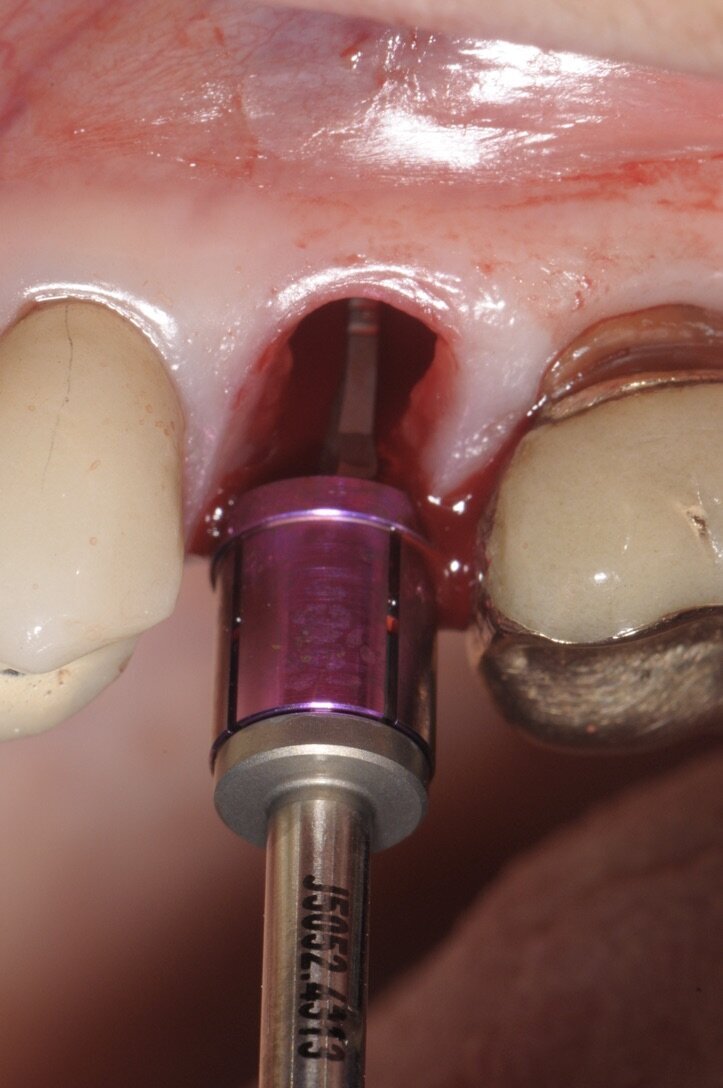

All’ispezione l’alveolo si presentava integro e ben conservato nel perimetro adiacente ai denti limitrofi, la scelta verso l’impianto immediato, nonostante l’evidente mancanza ossea residua oltre apice, che ci avrebbe permesso di ottenere una stabilità primaria apicale è stata comunque svolta grazie a un insieme di fattori concomitanti presenti come: l’uso di un impianto con forma similradicolare con il conseguimento di una stabilità primaria laterale oltre che apicale, pertanto procediamo con il sondaggio di una fresa a diametro crescente sino alla misura voluta che in tal caso era 4.3 mm (Fig. 4). Il taglio verticale delle frese hanno consentito di ottenere un recupero osseo utile per il riempimento di spazi residui. Prima di inserire l’impianto scelto (Conelog 4.3x13 mm-Camlog) procediamo ad ulteriore sondaggio con prova di Valsalva per escludere qualsiasi comunicazione col limitrofo seno mascellare. A procedura ultimata e a impianto inserito, la possibilità è duplice: o chiudere la ferita con un patch mucoso prelevato dal palato4 o posizionare una vite di guarigione sagomata, come nel caso in questione approfittando dello spessore palatino connettivale, prelevare un piccolo patch inserendolo vestibolarmente così da ridurre la morbilità per il paziente stesso e aumentando lo spessore connettivale ai fini estetici (Fig. 5)5.

Fig. 4 - Preparazione del sito implantare con la fresa del diametro dell’impianto impiegato.